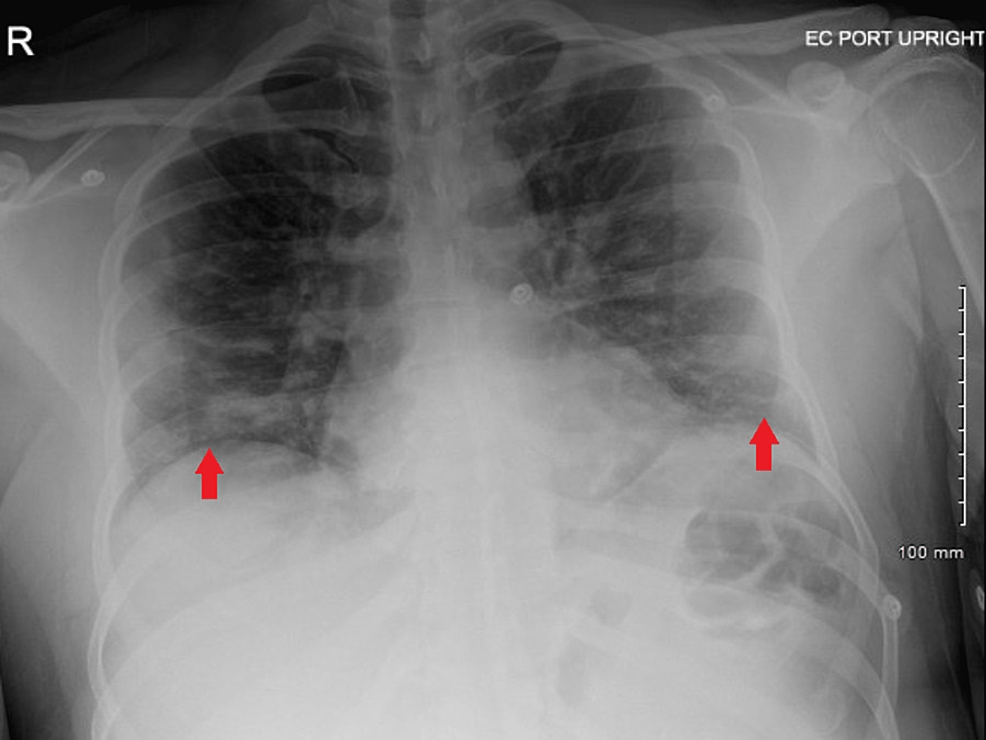

Chest X Ray Findings In Drowning . Patchy airspace opacification extending to pleural. Brain hypoxia manifest on ct by diffuse loss of. heart and mediastinal contours appear normal. it is thought to result from the inhalation of either fresh water or sea water resulting in lung damage and a ventilation. ap view of the chest demonstrates diffuse bilateral parenchymal opacities in the bilateral lungs, more confluent in the right.